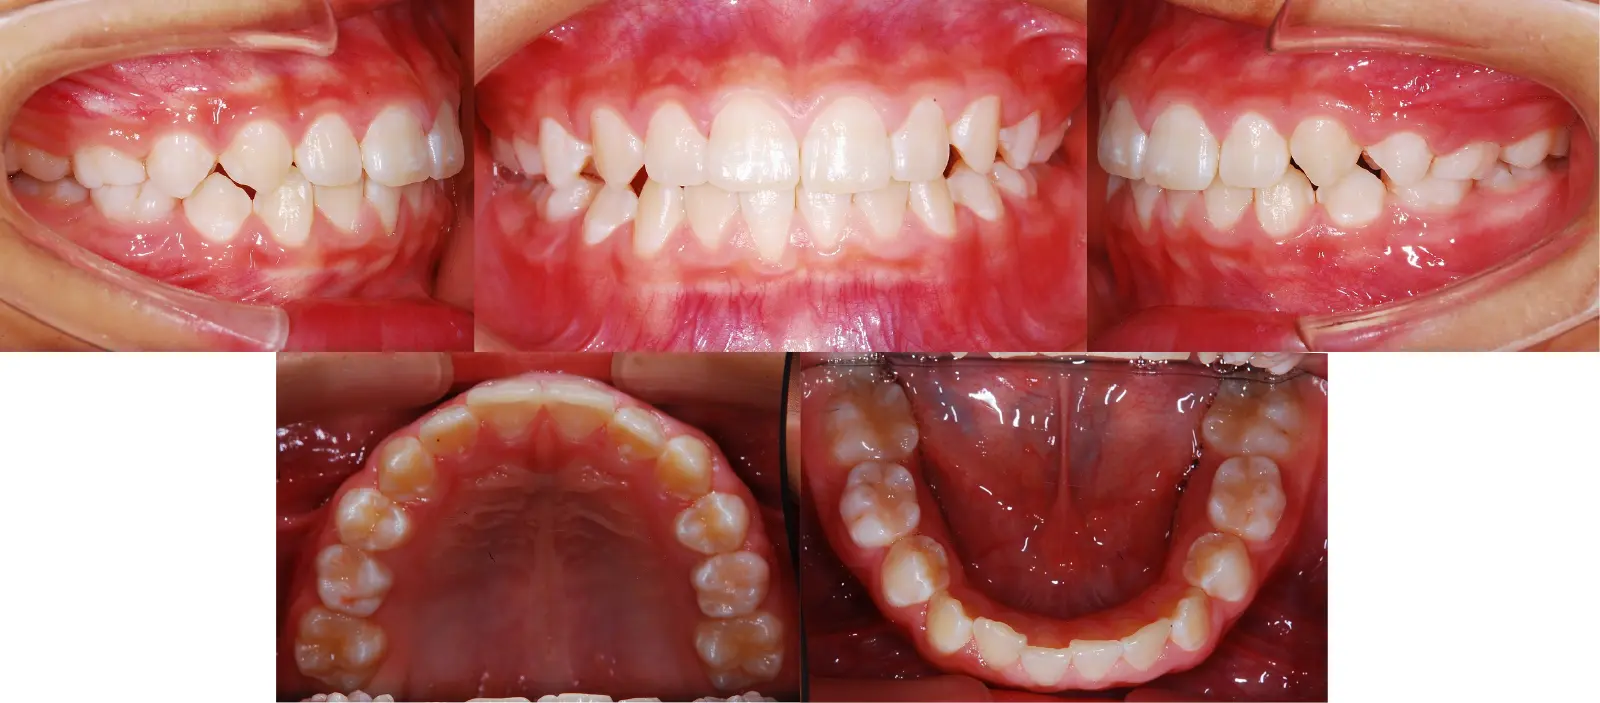

アングルⅠ級 反対咬合

第一段階の治療のみで、

永久歯は問題なく萌出し、安定している

- 主訴

1歯のみの逆破蓋

- 年齢

7歳

- 治療期間

6ヶ月

- 治療回数

6回

- 治療に用いた主な装置

2by2、拡大床

- 治療費

400,000円(税別)トータル料金

- 抜歯部位

非抜歯